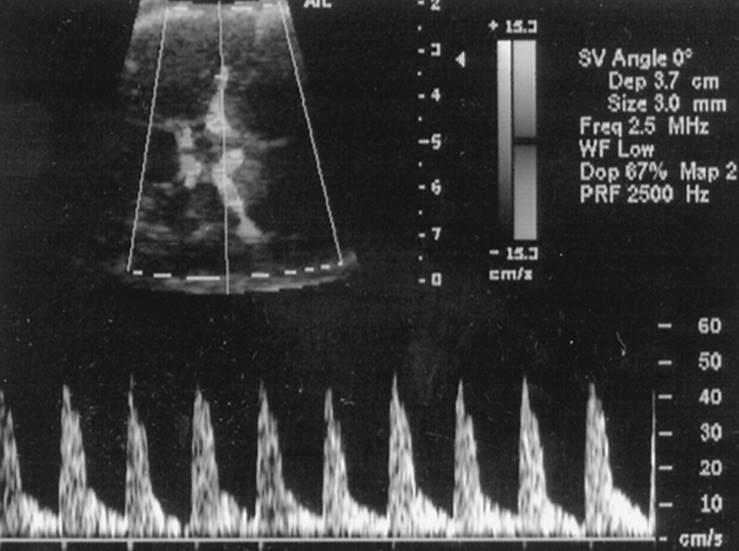

As mentioned earlier, Doppler velocimetry has been used to assess blood flow through the venous circulation of the IUGR fetus including the umbilical vein, ductus venosus, hepatic veins, and IVC. The IVC and the ductus venosus essentially represent the preload profile of the cardiovascular system. Interesting information conveyed by research on these vessels is the significant correlation between abnormal changes in the vessels and acid-base changes of the fetus. Others have correlated these Doppler indices with fetal heart monitoring patterns. Abnormalities in the ductus venosus are characterized by a decrease in velocity of the a-wave, and if the fetus continues to deteriorate, the ductus venosus may show absent or reversed flow velocity of the a-wave. The ductus venosus waveform in a severely growth restricted fetus from 20 to 22 weeks gestation of a mother with severe renal disease and hypertension is shown in Figure 12.5. The a-wave at 20 weeks showed reasonable flow velocity, but progressively deteriorated to intermittent absent and reverse flow velocity.

FIG. 12.5. Ductus venosus flow velocity waveform with abnormal a-waves in a severely growth restricted fetus admitted at 20 weeks gestation. Note the progressive decrease in velocity of flow in the a-wave.